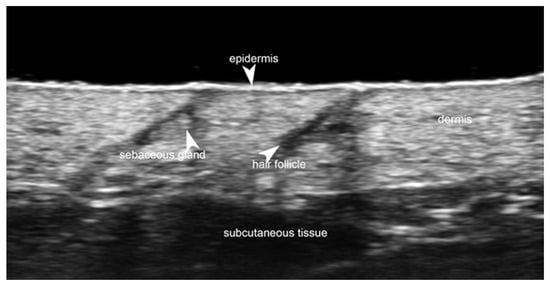

5. Specific Cutaneous Structure and Sites of Skin Disorders